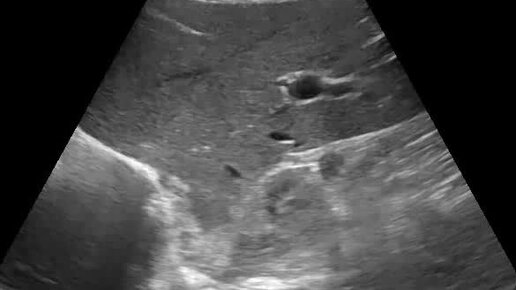

Аденома печени

Ультразвуковые находки от врача УЗД Зорина Я.П.